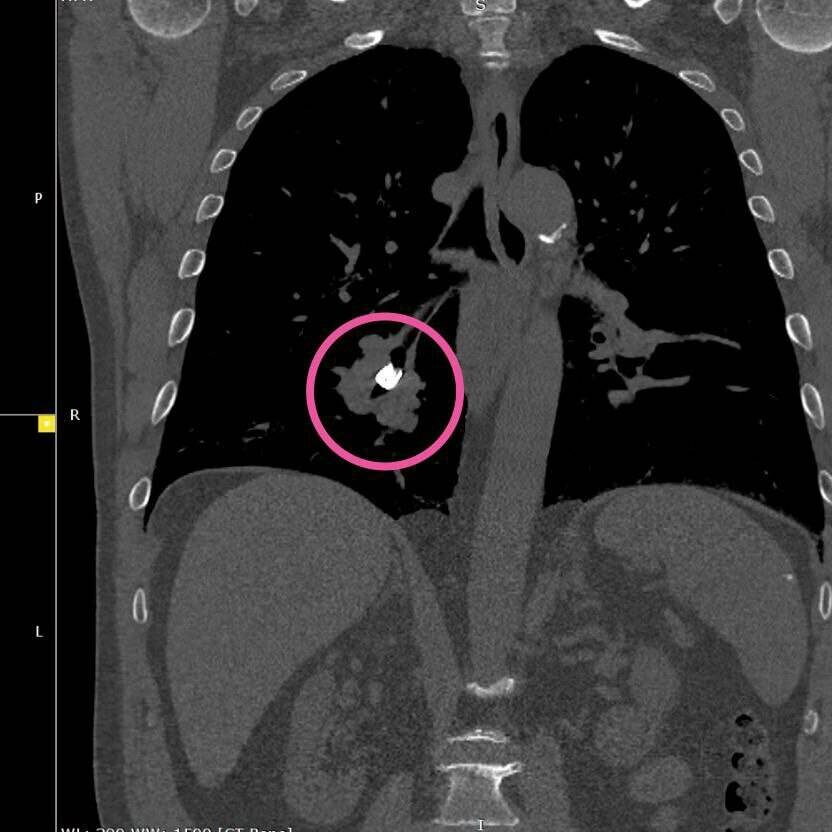

Была проведена компьютерная томография органов грудной клетки. В бронхах обнаружилась зубная коронка. Мужчину госпитализировали в отделение торакальной хирургии №1 РКБ.

Фото: РКБ Татарстана